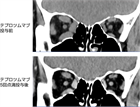

1. 活動期の甲状腺眼症に対して完全ヒト型抗インスリン様成長因子1受容体(IGF-1R)阻害剤であるテプロツムマブの点滴静注治療が2024年11月にわが国で認可された